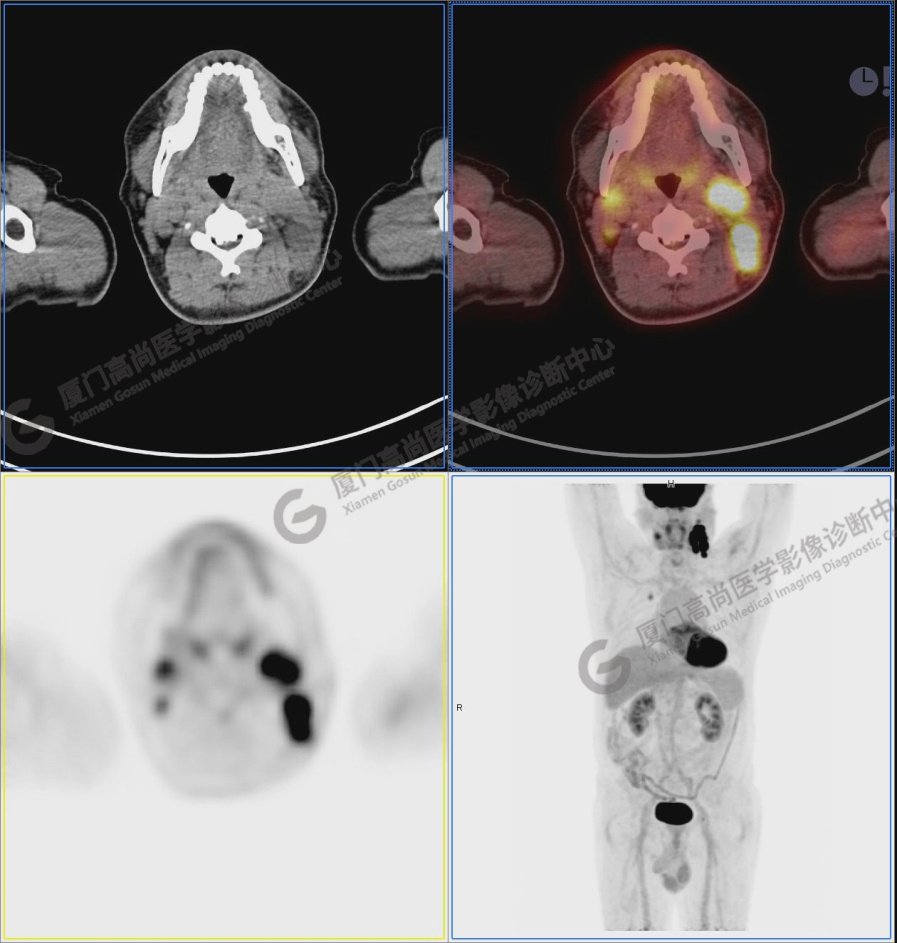

圖1:PET/CT全身圖像

圖2:雙側(cè)頸部多發(fā)增大淋巴結(jié),代謝不同程度增高,考慮為轉(zhuǎn)移。

圖3

圖4